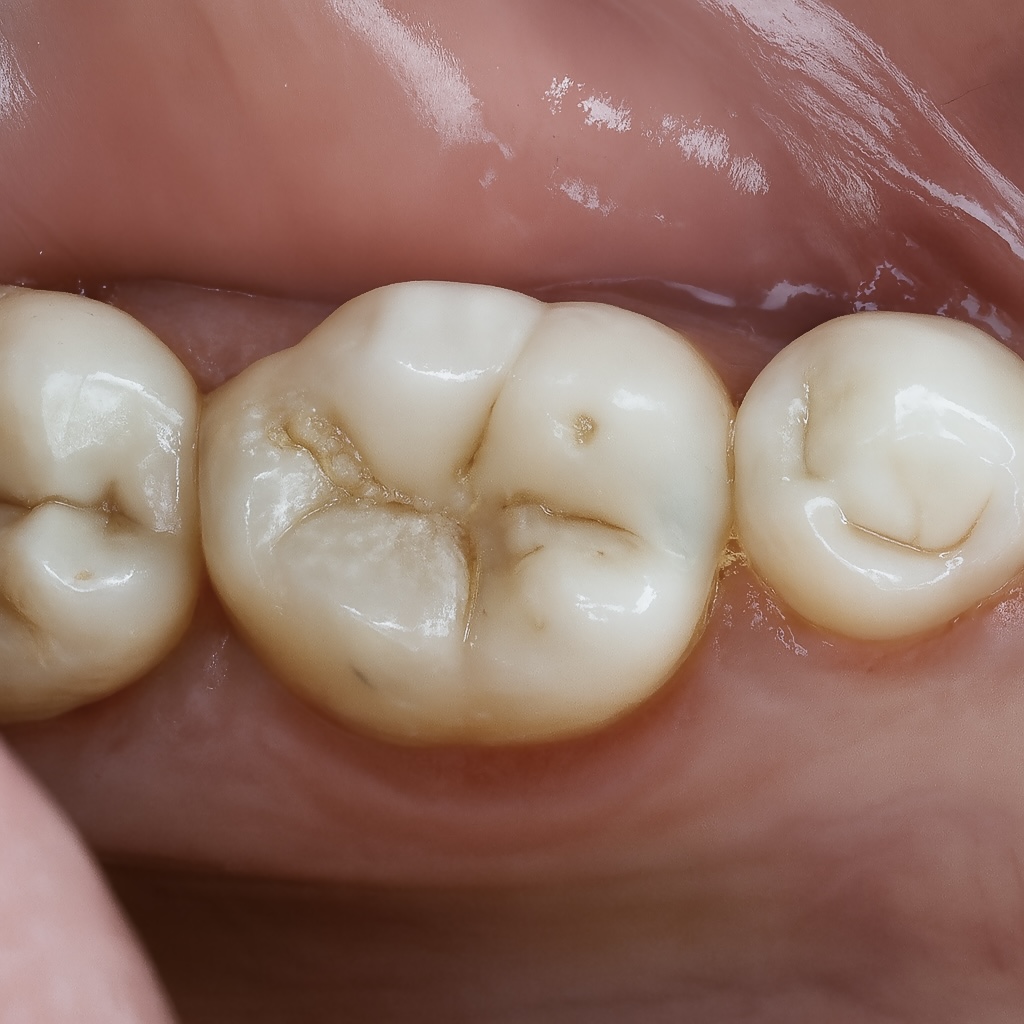

4.6 Finishing & Polishing

Finishing was done using:

- Fine diamond for gross adjustment

- Sof-Lex discs for contour

- Silicone polishers for luster

- Final gloss achieved with Diashine (your signature finish)

The occlusion was verified in maximum intercuspation and excursive movements.

5. OUTCOME

- Tight, healthy proximal contact

- Excellent emergence profile that supports papilla health

- Natural occlusal anatomy

- Smooth margins fully blended with adjacent enamel

- Zero postoperative sensitivity

- Patient reported immediate improvement in chewing comfort

The final clinical photos and radiographs reflect a clean, predictable, and biologically respectful restoration.